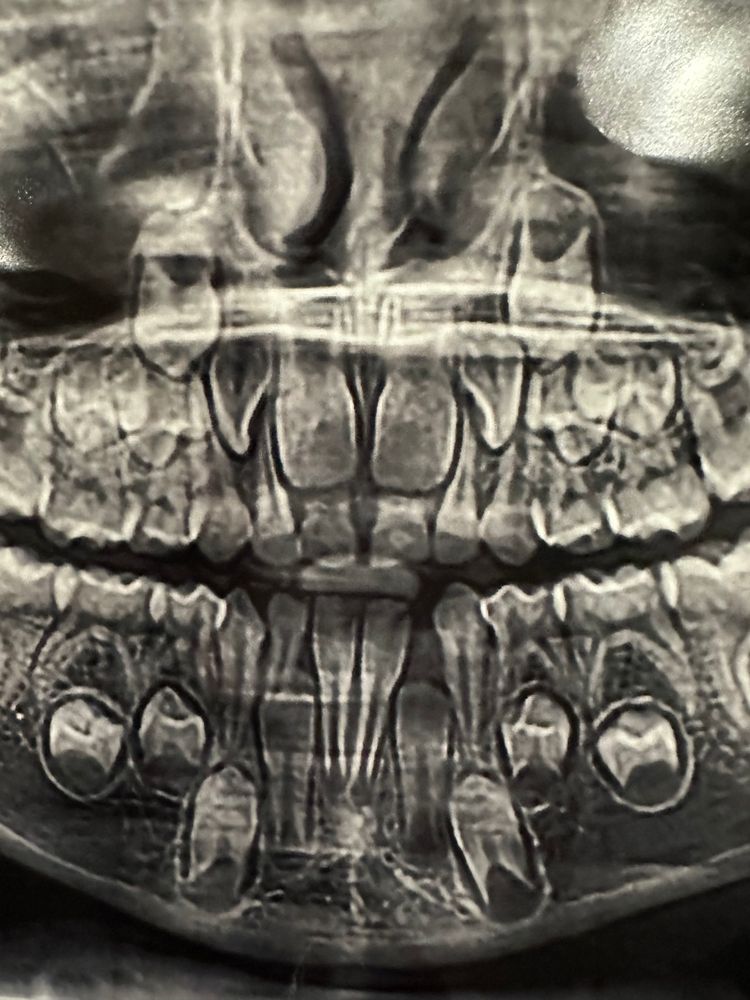

Клыкообразные двойки

Ходили с младшей к ортодонту, рекомендовали аппарат хааса ставить. Ок, доктору виднее) сначала, само собой, снимок. И тут я вижу эти двойки😳 конечно, спрошу ещё у врача, что это, но любопытно же, может кто сталкивался и знает, почему верхние коренные двойки такой странной формы. Они повернуты? Или и правда будут клыкообразные?